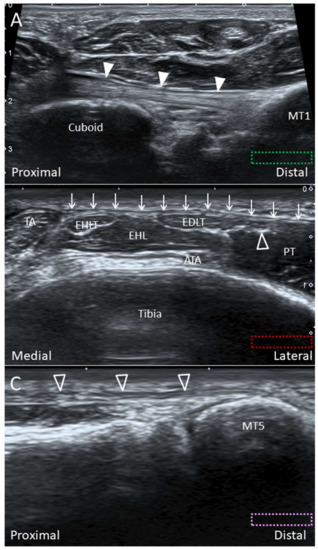

4.2. Peroneus Tertius Tendon

4.2.1. Anatomy

4.2.2. Scanning Technique

4.2.3. Clinical Relevance

3.2. Scanning Technique

3.3. Clinical Relevance